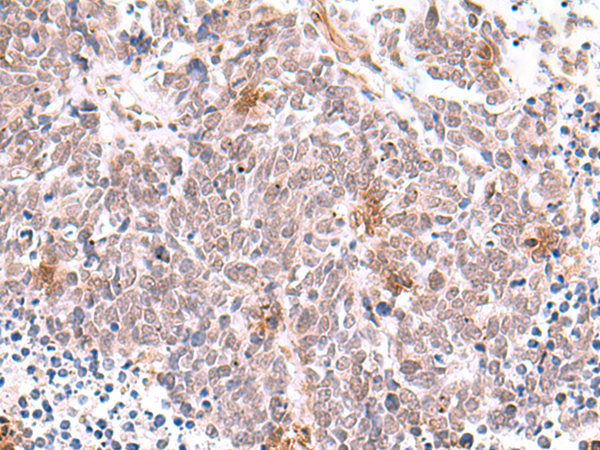

IHC positive control:

Human tonsil and Human lung cancer

IHC Recommend dilution:

50-300